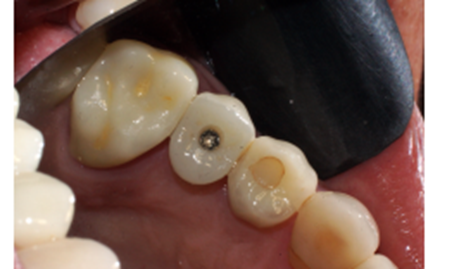

Foi eleito um implante Veloce Cone Morse de 3.75 X 11.5 mm e após a exodontia, o implante foi instalado utilizando o protocolo de fresagem recomendado pelo fabricante, fazendo uso das fresas escalonadas do sistema, alcançando um torque de inserção de 70 Ncm, o que me incentivou a promover o carregamento imediato deste implante (Figuras 5, 6, 7, 8, 9 e 10).

Diante das circunstâncias, foi eleito um pilar Ideale reto de 3.3 X 4.0 X 1.5 mm de transmucoso, que foi instalado a 20 Ncm. O escaneamento desse pilar foi realizado para a confecção de um provisório fresado em PMMA. Após 15 minutos da instalação e do escaneamento do pilar, o provisório fresado foi instalado sobre o pilar Ideale e aparafusado com o parafuso Torx a 10 Ncm. Foi então realizada uma radiografia após a instalação e a paciente foi marcada para retornos de 7 e 15 dias, sendo que após os retornos, a paciente realizou sua viagem (Figuras 11, 12, 13 e 14).